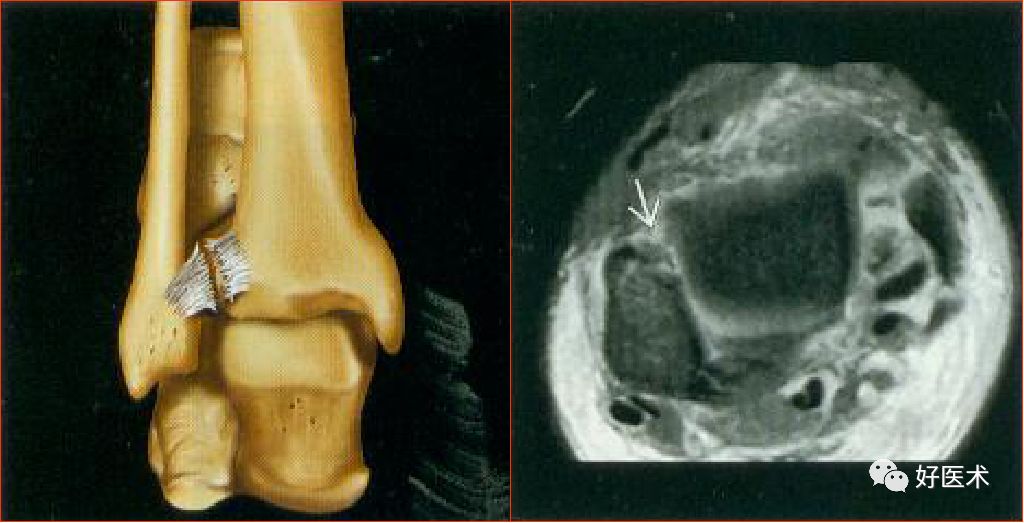

联合韧带

胫腓前后韧带:位于胫距关节上方,连接外踝前、后面与胫骨前、后结节,起支持作用

胫腓横韧带:位于胫腓后韧带前下方,后外踝延伸至胫骨关节面后缘,恰好位于内踝的外侧

联合韧带(胫腓前韧带)撕裂